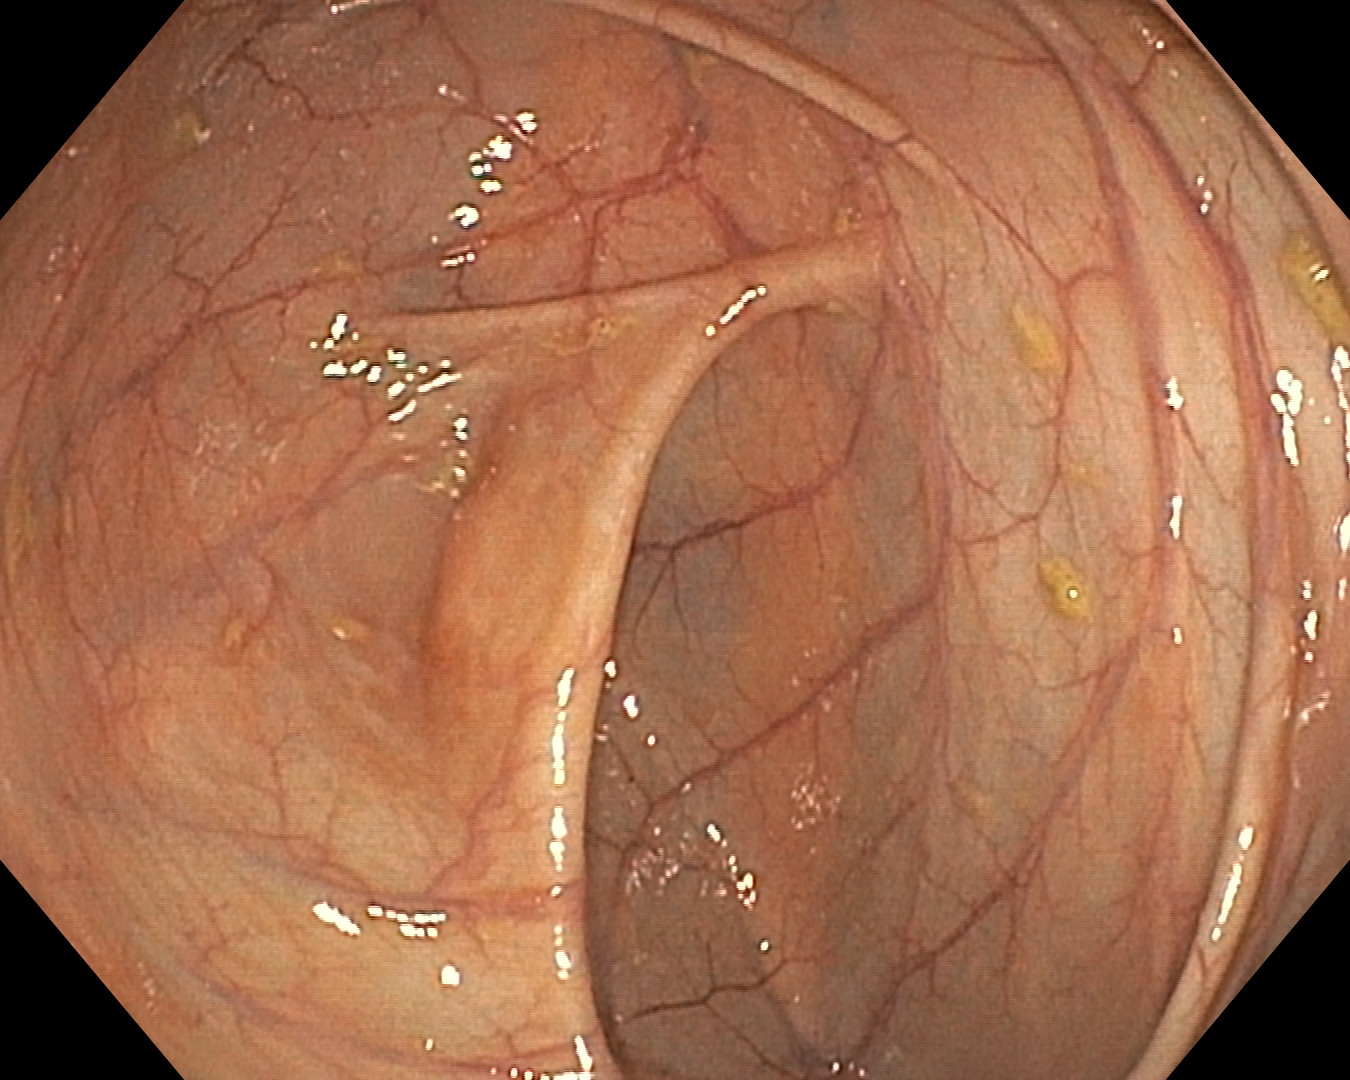

As part of the EndoCV2021 challenge (https://endocv2021.grand-challenge.org/), we were tasked with creating machine learning models that automatically segment polyps [11, 12, 13] in video frames collected from real-world endoscopies. This is a complex task as polyps come in various shapes and sizes, where some (e.g., flat lesions) are barely detectable by even the most experienced endoscopists. Figure 1 shows some of the more difficult examples taken from EndoCV’s development dataset [10] provided by the challenge organizers. The challenge presented two separate tasks, the detection generalization challenge and the segmentation generalization challenge. We participated in the segmentation generalization challenge, where we achieved the best results among 13 other competitors in both rounds. The code for the experiments presented in this paper is available on GitHub111https://github.com/vlbthambawita/divergent-nets.